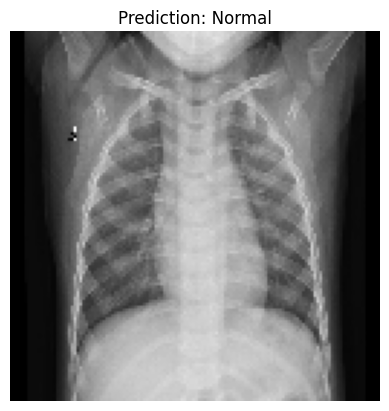

Testing the Model with a Sample Image “Now comes the exciting part—testing our model on a sample image. Let us see how well it predicts pneumonia or normal lungs. Here’s the code for that.”

sample_image_path = 'chest_xray/chest_xray/test/NORMAL/NORMAL2-IM-0035-0001.jpeg'

sample_image = load_img(sample_image_path, target_size=(128, 128))

sample_image_array = img_to_array(sample_image) / 255.0

sample_image_array = np.expand_dims(sample_image_array, axis=0)

# Make a prediction

prediction = model.predict(sample_image_array)

# Display the image with the prediction

plt.imshow(sample_image)

plt.title(f"Prediction: {'Pneumonia' if prediction[0][0] > 0.5 else 'Normal'}")

plt.axis('off')

plt.show()1/1 ━━━━━━━━━━━━━━━━━━━━ 0s 104ms/step

Step-by-Step Explanation

1. Loading the Image: “We first load a sample X-ray image using the load_img() function. Make sure the path to the image is correct. - The target_size=(128, 128) resizes the image to match the input size of our CNN.”

img_to_array(). Dividing by 255.0 normalizes the pixel values, just like we did for the training data.np.expand_dims() to make it compatible with the model input.”Making Predictions: “The model.predict() function generates a prediction. If the value is greater than 0.5, the model predicts ‘Pneumonia’; otherwise, it predicts ‘Normal’.”

Displaying the Image: “Finally, we use Matplotlib to display the image along with the prediction. Isn’t it satisfying to see our model in action?”